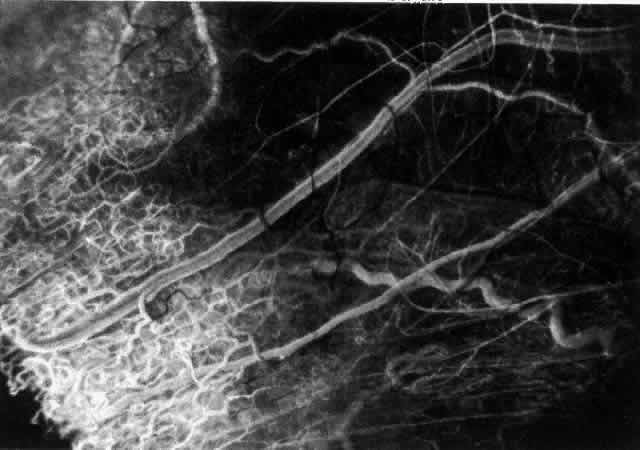

With the increasing use of anterior segment fluorescein angiography in the early detection of severe necrotizing disease of the sclera, it is necessary to have an understanding of the normal anatomy of the vasculature of the anterior segment of the eye.3–5 The blood supply to this region is enormous, being derived from the anterior ciliary arteries, but with extensive collateral arterial anastomoses to the posterior ciliary arteries at the root of the iris (Fig. 1). The anterior system is readily visible with the slit lamp and by anterior segment fluorescein angiography, especially if the eye is inflamed, and its recognition is of vital importance in the differentiation of episcleral and scleral conditions. The separation and displacement of these vascular layers give the most important clinical clues to the site and, hence, the severity of the inflammation. On slit lamp examination, three layers of vessels are readily visible. The conjunctival plexus, which is the most superficial layer of vessels, can be moved over the underlying structures. The superficial episcleral capillary plexus (Fig. 2) is a radially arranged series of vessels lying within the parietal layer of Tenon's capsule. The vessels in this layer anastomose at the limbus with the conjunctival vessels, with other members of the same plexus, and with the deep plexus. The deep episcleral capillary network (see Fig. 2) is closely applied to the sclera in the visceral layer of Tenon's capsule. The vessels anastomose freely with each other, forming a syncytium. The large vessels to and from the intrascleral plexus traverse the episclera near the insertions of the muscles. The conjunctival and superficial episcleral vessels can be blanched with 1:1000 epinephrine or 10% phenylephrine, but the deep vessels are affected slightly. This is of considerable assistance when attempting to differentiate deep and superficial inflammation.

Fig. 1. Anterior view montage of a cynomolgus monkey ocular casting with Tenon's and episcleral vessels removed. The anterior ciliary arteries (ACA) arborize at the limbus and interconnect via their lateral branches to form the episcleral circle. (CM, ciliary muscle capillary bed; CV, choroidal veins; EC, episcleral circle. (Original magnification, X20). (Morrison JC, van Buskirk EM: Anterior collateral circulation in the primate eye. Ophthalmology 90:707, 1983)